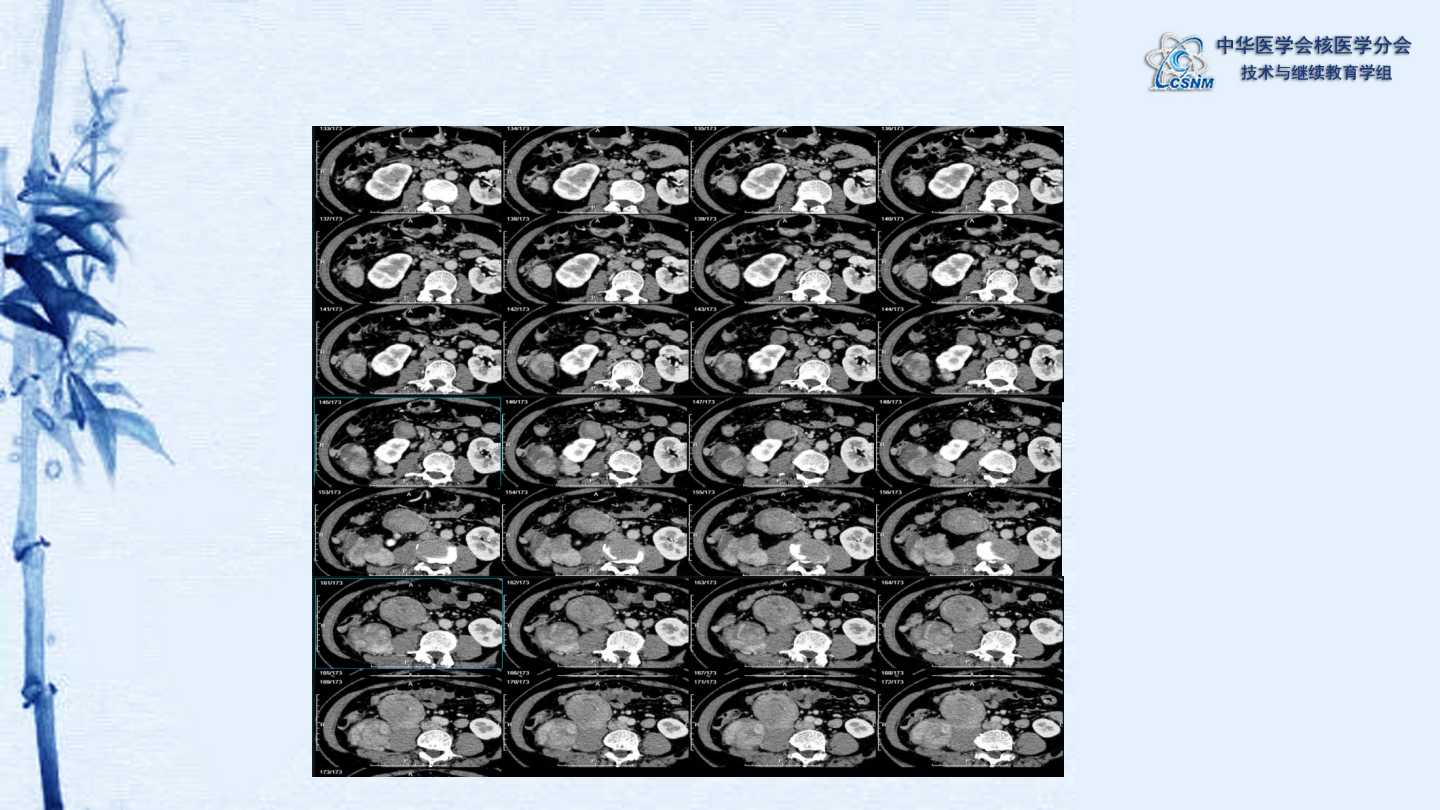

【CSNM继教学组】病例E51-邢岩-结肠炎性肌纤维母细胞瘤18F-FDG PET/CT显像